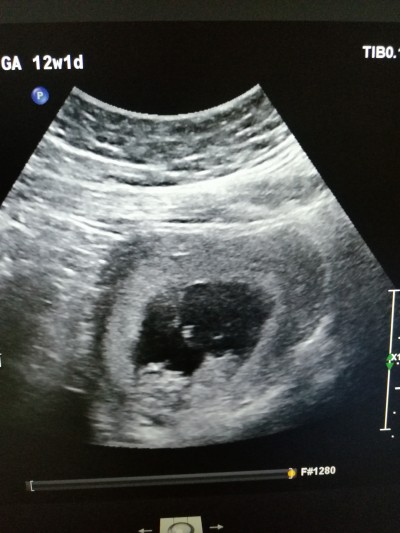

11+3 günlük nub teorisi bilen tahmin edebilir mi

Kiz bnce nub a göre düz çünkü

Bence erkek Bebek diyorum